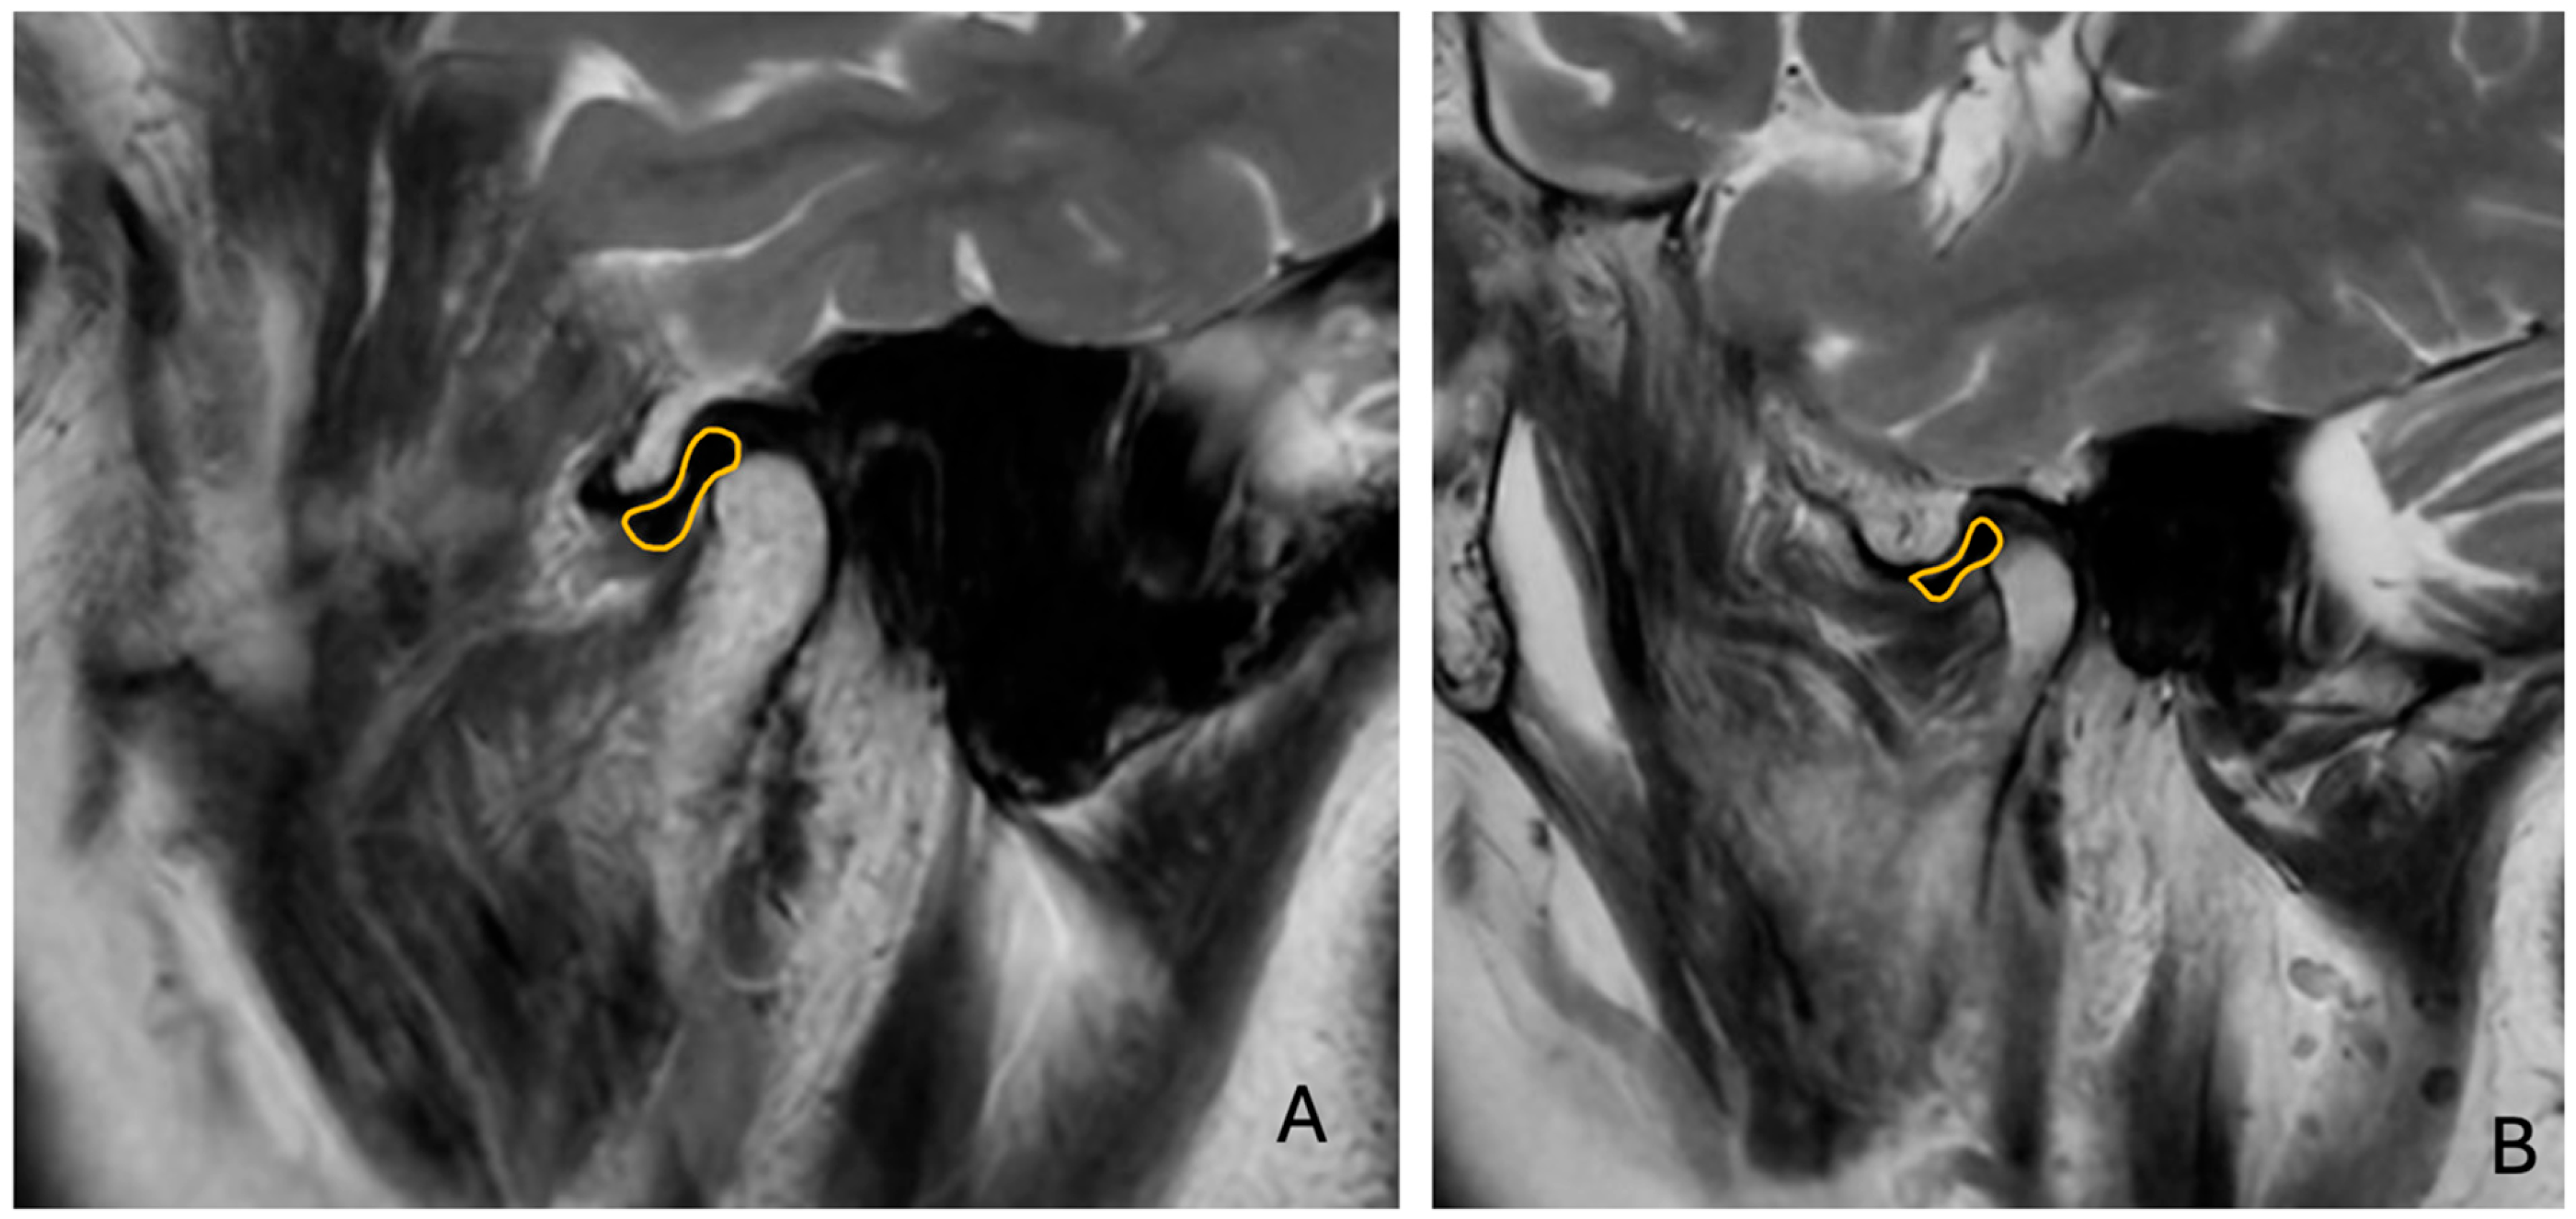

Sagittal T1W and T2W images were analyzed to determine the relationship between the TMJ condyle and articular disc (Figure 3).

The presence of anterior disc displacement (ADD) was classified using the Research Diagnostic Criteria for Temporomandibular Disorders (RDC/TMD) [5], considering the position of the disc relative to the condylar head and articular eminence in closed-mouth positions. Disc displacement is based on the position of the articular disc relative to the condylar head and articular eminence in the closed-mouth position. Anterior disc displacement is diagnosed when the disc is positioned anterior to the condyle. CT images were examined for TMJ hard tissue changes and to classify condylar morphology based on established radiographic criteria (Figure 4):

Figure 3. T2-weighted MR images of ((A) right and (B) left) disc displacement in closed-mouth position. Yellow areas show temporomanidbular disc.